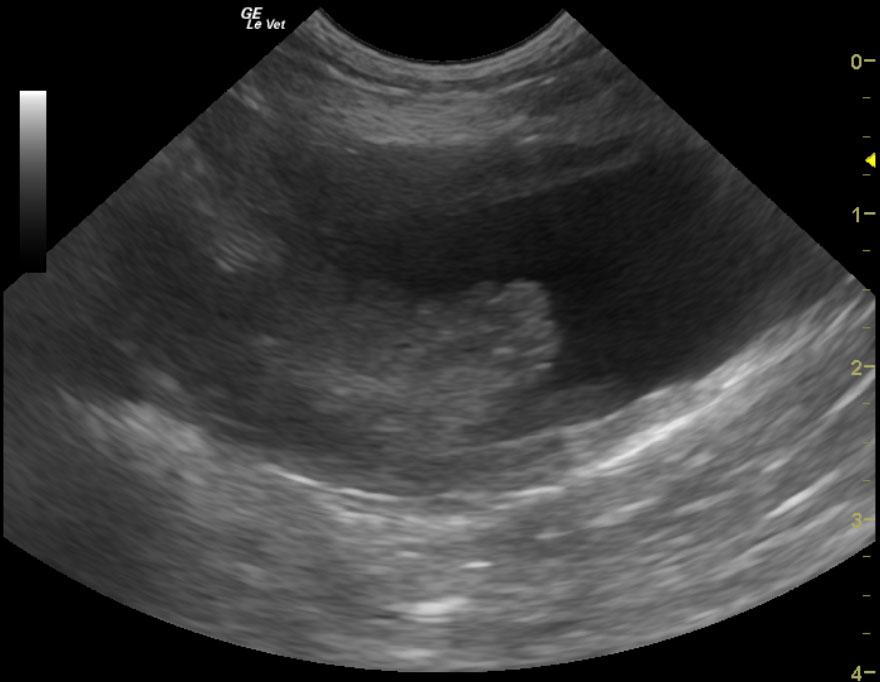

A 10-year-old neutered male West Highland Terrier was presented for hematuria. The only finding on physical examination was a soft cardiac murmur. Abnormalities on urinalysis were 1+ bilirubin and trace blood.